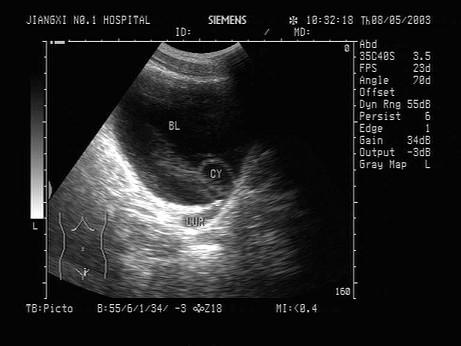

问题 女性,5岁,超声检查如图所示,最可能的诊断是?(?)

选项 A.输尿管脱垂 B.输尿管憩室 C.输尿管囊肿 D.输尿管肿瘤 E.巨输尿管症

答案 C